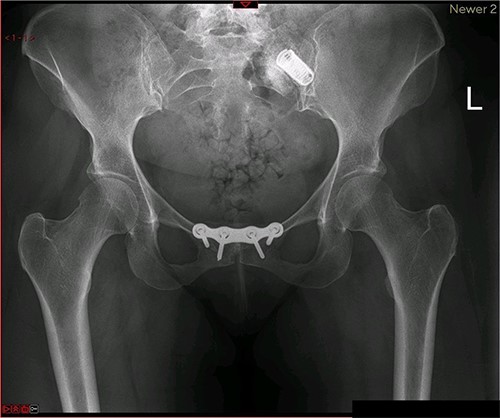

A magnetic resonance imaging (MRI) scan performed in October 2013 (Fig. 1) identified non-compressive, degenerated discs at L4/5 and L5/S1 vertebral levels. However, clinically as the patient was more tender over the left SI joint and the pubic symphysis (Fig. 2), a left sacroiliac joint fusion and symphysis pubis plating procedure was performed in August 2014 (Fig. 3). Following a short period of relief, the pain returned. Subsequently, the patient underwent a 360° fusion (front and back) of the L4/L5 and L5/S1 discs in August 2015 (Fig. 4), a year following the previous surgery. Once again, following a brief period of relief, the symptoms returned. The assumption then was that the initial fusion of the left sacroiliac joint had failed. Therefore, a revision fusion of the left sacroiliac joint and a primary fusion of the right sacroiliac joint was undertaken in August 2017 (Fig. 5).

Postoperative X-ray of the pelvis following the second fusion surgery: postoperative X-ray of the pelvis, performed in January 2016 following the second fusion surgery, showing 360° (front and back) fusion of the L4/5 and L5/S1 disc space.